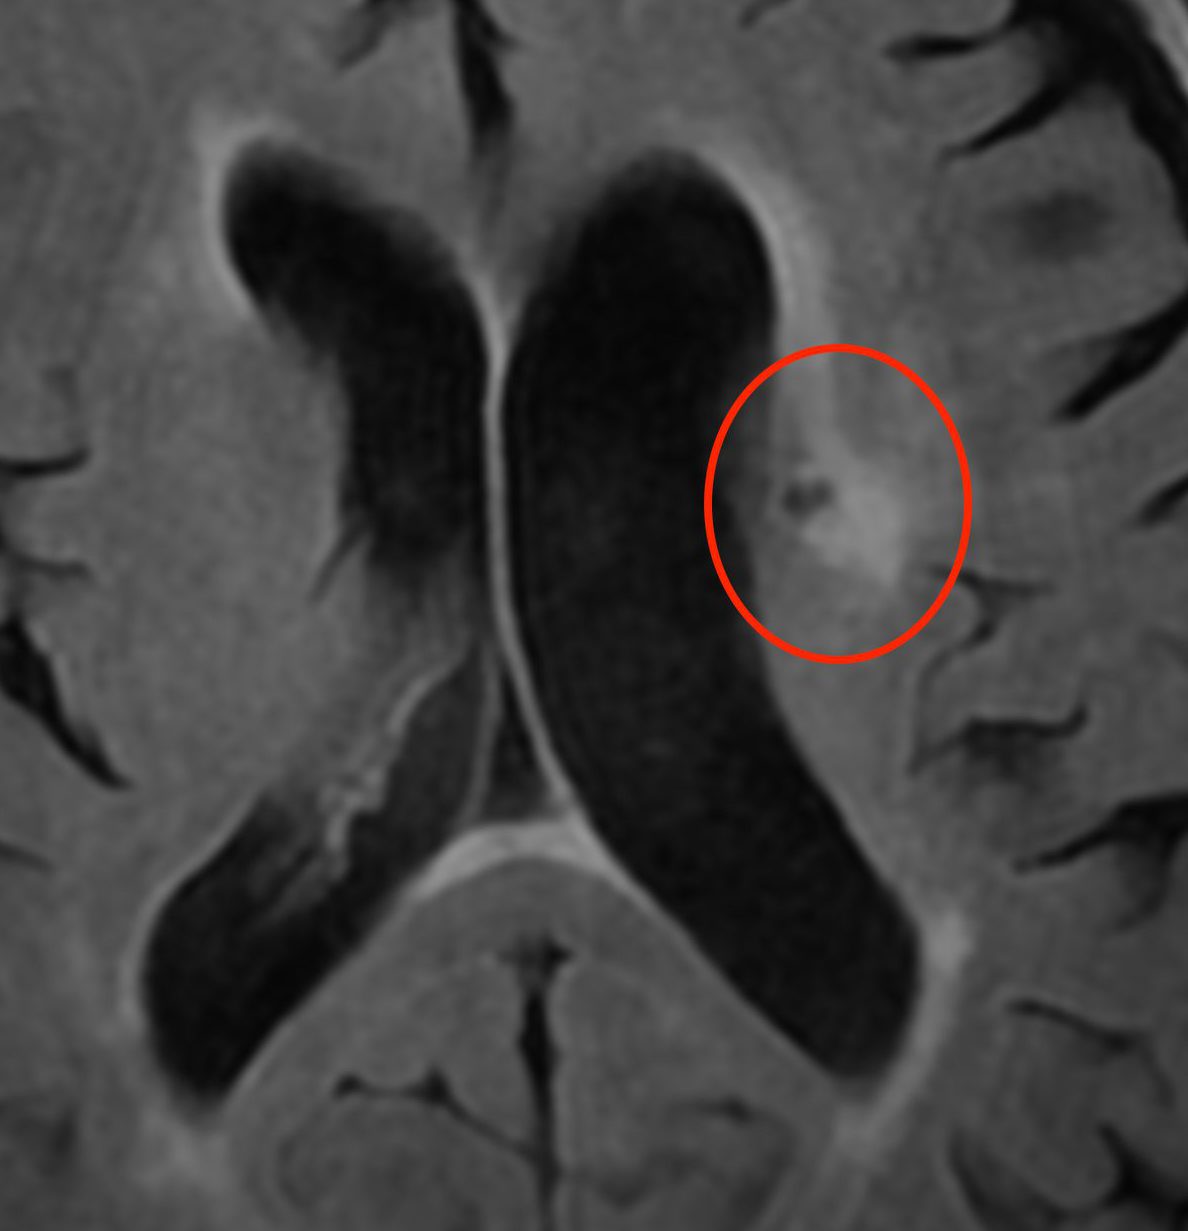

微小脳梗塞

これらの状態はいずれも無症状です。悪化した場合、後遺症が残る可能性もあるため、高血圧症や糖尿病のコントロールが必要です。